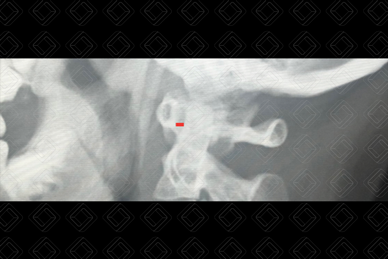

Texto alternativo para a imagem Figura 2. Créditos: Dra. Elazir Mota - Rio de Janeiro/RJ

Descrição da figura 2: Localizada da coluna cervical para mostrar o local onde deve ser medida em cada posição, a distância entre a face posterior do arco anterior do atlas (C1) e a face anterior do processo odontoide de C2 (o valor considerada normal é menor ou igual a 4 mm) – marcação em vermelho da distância.

Rotina radiográfica da coluna cervical: Para adequada avaliação de instabilidade da articulação atlantoaxial, o estudo deve ser efetuado com a realização de três radiografias da coluna cervical em perfil, em três diferentes posições: neutro, flexão e extensão. Nas três incidências realizadas, o radiologista mede a distância entre a face posterior do arco anterior do atlas e a face anterior do processo odontoide de C2 (o valor considerada normal é menor ou igual a 4 mm) (figuras 1 e 2).